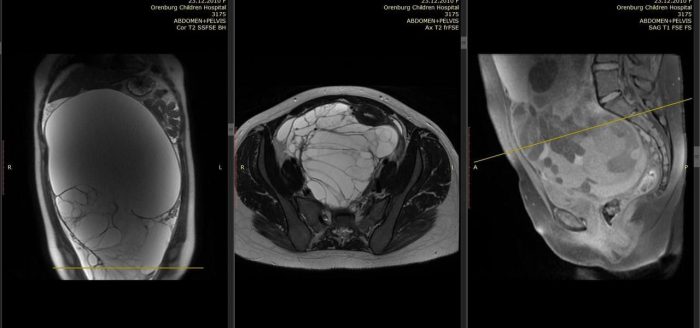

Девочку доставили в экстренное приёмное отделение ОДКБ с жалобами на сильные тянущие боли после физнагрузки. У ребенка было чувство распирания при положении «лежа на животе», сильно вырос живот. УЗИ и МРТ показали плотное объемное образование гигантских размеров 35 х 24 х 16 см, занимающее всю брюшную полость.

Врачи поставили диагноз гигантская муцинозная цистаденома яичника. Такая опухоль требует срочной операции. Ситуацию осложняли побочные диагнозы: гидронефроз правой почки, который возник следствие того, что органы были сильно сдавлены.

В итоге медики выполнили лапаротомию. Образование, которое весило 8 кг, удалось удалить полностью.